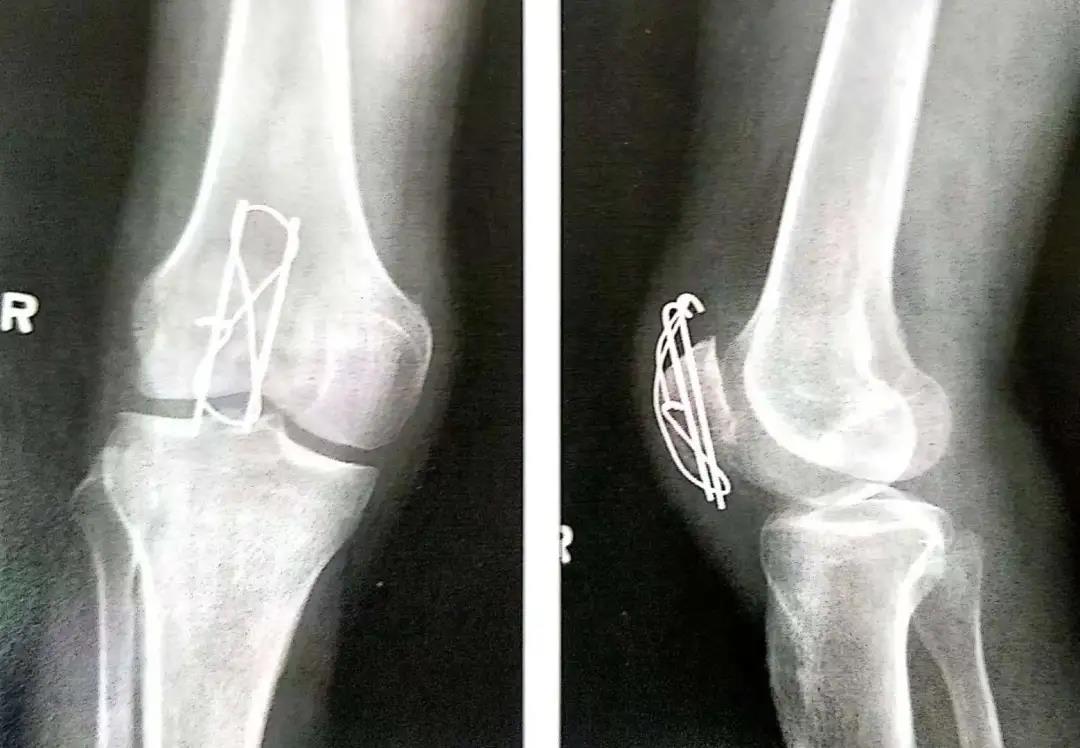

- 顺行或逆行打入克氏针。

- 克氏针或螺丝钉应在髌骨前皮质面下大约5mm打入,在骨质内冠状面和矢状面上相互平行。

- 在穿过骨折线之前,可用术中透视(正位和侧位)直视下或将手指伸到髌骨下触摸的方式来确保骨折已复位。